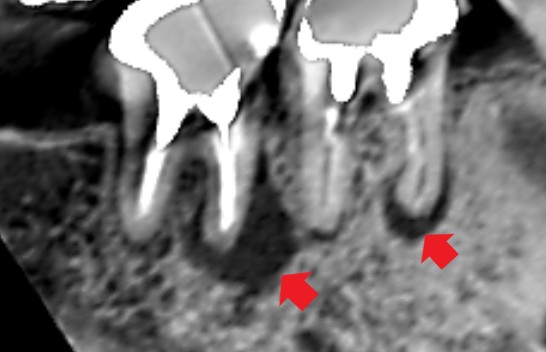

右下の第一大臼歯と第二大臼歯の初診時のCT画像です。

第一大臼歯と第二大臼歯それぞれの根の先に膿の影がみられます。口腔外科では抜歯の診断でしたが、精密再根管治療により改善する可能性もあると診断しました。